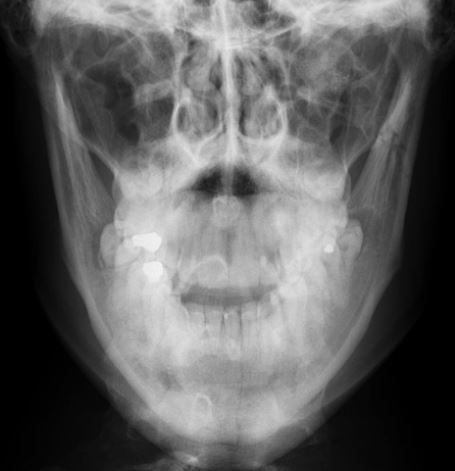

X-RAY QUIZ: Which finding is present on this image?

B: Sail sign

C: Meniscus sign